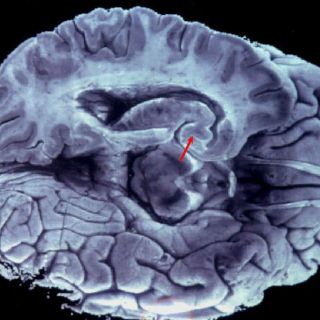

BRUSELAS, BÉLGICA (28/MAR/2013).- La Universidad Libre de Bruselas (ULB) inauguró hoy aquí su Instituto de Neurociencias (UNI), un centro de investigación multidisciplinar sobre el cerebro que reune a más de 150 investigadores de 17 laboratorios y cuatro disciplinas.

El objetivo es reunir los conocimientos de las áreas de neurofisiología, neuro-imagen y las neurociencias moleculares y cognitivas para buscar respuestas a enfermedades del sistema nervioso aún mal conocidas y que afectan a 2.9 millones de personas sólo en Bélgica.

"Es necesario un nuevo enfoque para comprender tanto el desarrollo del cerebro como la degeneración de sus funciones cognitivas que conducen a enfermedades como Alzheimer o Parkinson", apuntó.